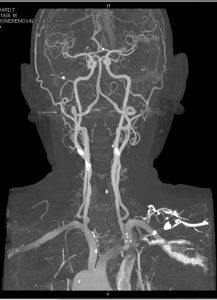

КТ-ангиография сосудов головы и шеи - диагностический метод, позволяющий послойно просканировать кровеносное русло и преобразовать снимки в детализированную трехмерную картинку. На основании полученных данных врач-рентгенолог делает заключение о наличии либо отсутствии нарушений.

Компьютерная томография сосудов головы и шеи - объемная реконструкция

3D-КТ-ангиография сосудов головного мозга

Фото КТ сосудов головы и шеи

На снимках ангиографии шейных и головных сосудов визуализируются:

крупные артерии со своими ветвями:

передняя, средняя, задняя мозговые артерии и сосуды, участвующие в образовании Виллизиева круга вместе с ними;

сонные (общая, наружная, внутренняя);

позвоночные и основная артерия;

синусы твердой мозговой оболочки;

КТ шейных сосудов (объемная реконструкция). На изображении можно увидеть пример кинкинга (патологической извитости) и аневризм (колбовидных расширений) экстракраниальных сегментов внутренних сонных артерий

Также по фото компьютерной ангиографии выявляют коллатерали - обходные кровеносные пути, активизирующиеся при проблемах с проходимостью магистральных артерий (окклюзии, стенозе, повреждениях и т.д.).

Компьютерные томограммы сосудов головного мозга и шеи